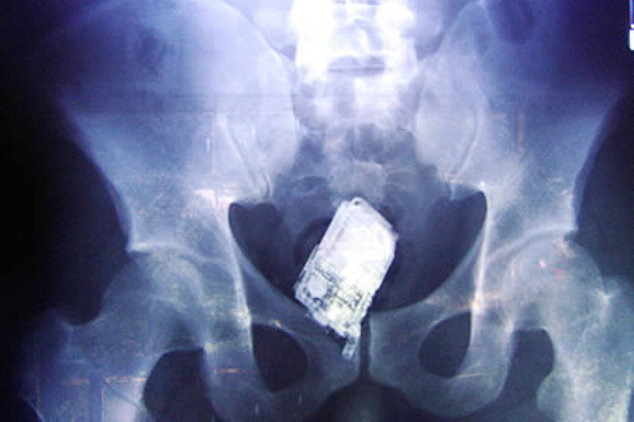

Sinar X adalah teknologi mutakhir yang memudahkan para dokter untuk melihat isi tubuh manusia tanpa harus membedahnya. Bukan hanya organ yang kelihatan, kadang-kadang para dokter juga menemukan perkakas seperti kunci mobil, ponsel hingga botol minum yang terjebak di dalam tubuh pasien. (Foto: Pool)![]() Nicholas Holderman, seorang laki-laki asal Kentucky mengalami cedera fatal saat terjatuh. Kunci mobil yang dipegangnya menancap di wajah, menembus kelopak mata dan tulang tengkorak hingga ke otak. Beruntung, tidak ada kerusakan permanen yang dialaminya. (Foto: The Times) ![]() Laki-laki 60 tahun asal Multan, Pakistan mendatangi Nishtar Hospital dengan keluhan yang agak janggal, sejanggal hasil pemindaian dengan sinar X. Sebotol minuman bersoda merek Pepsi terjebak di anusnya, konon dimasukkan secara paksa oleh seorang penjahat yang kepergok akan mencuri 2 ekor sapinya. (Foto: Reuters) ![]() Fateh Mohammad, seorang napi di Pakistan mengaku tidak tahu apa-apa saat bangun pagi dan merasa ada yang tidak nyaman di anusnya. Mungkin ada teman satu sel yang jahil, hasil pemindaian dengan sinar X menunjukkan ada bohlam lampu pijar terjebak di anusnya. (Foto: Typepad) ![]() Lewat pemindaian dengan sinar X, tim dokter di di El Savador menemukan sebuah ponsel di usus halus. Pasien yang merupakan anggota geng Mara Salvatrucha merupakan 1 dari 4 napi yang berusaha menyelundupkan ponsel ke penjara namun gagal karena setelah ditelan ponsel tersebut tidak bisa keluar lagi. (Foto: CBS News) ![]() Tim bedah kandungan di sebuah rumah sakit panik saat foto sinar X menunjukkan ada pistol terjebak di vagina seorang pasien, dengan posisi seperti sudah terkokang dan siap ditembakkan. Operasi dilakukan dengan rompi antipeluru, tapi setelah dikeluarkan ternyata hanya korek gas yang bentuknya mirip pistol. (Foto: Neatorama) Sumber : http://health.detik.com/readfoto/2012/09/03/100214/2005786/1406/5/yang-horor-dari-sinar-x#viewfoto |